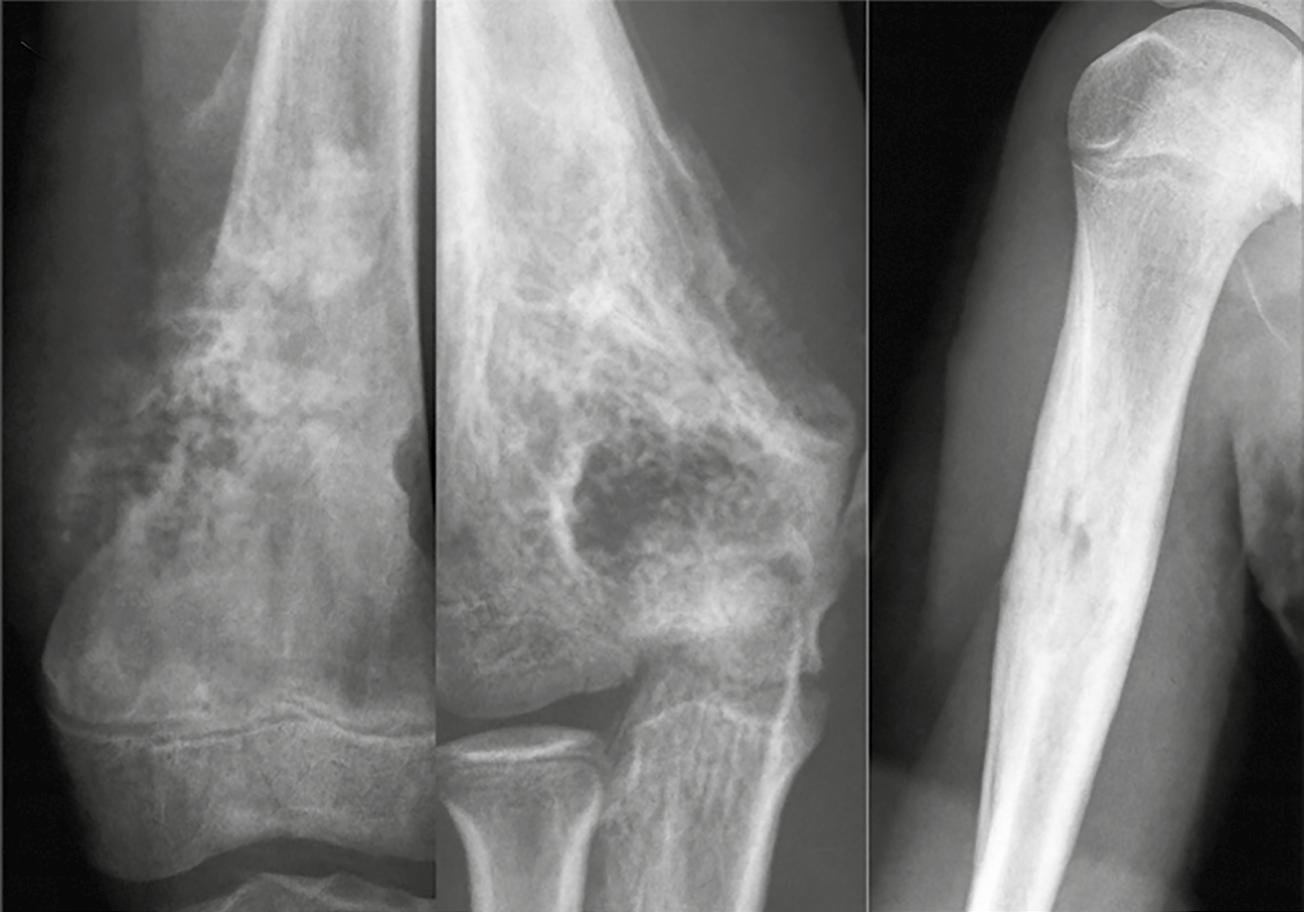

Determinar si la lesión se encuentra en la epífisis, metáfisis o diáfisis contribuye a delimitar el espectro de posibilidades diagnósticas. La ubicación anatómica de una lesión ósea dentro del esqueleto puede ofrecer pistas valiosas en el diagnóstico diferencial. Algunos tumores tienen afinidad por ciertas regiones óseas, lo cual, junto con la edad y el patrón radiológico, puede orientar al clínico. Por ejemplo, en zonas como el húmero o alrededor de la rodilla, es común encontrar una amplia variedad de tumores. La Figura 10 y la Tabla 6 agrupan las localizaciones tumorales óseas más frecuentes, lo que permite relacionar patrones de presentación con diagnósticos probables.

La Tabla 7 nos muestra las localizaciones anatómicas más frecuentes.

La localización anatómica de una lesión ósea puede ofrecer pistas valiosas para orientar el diagnóstico (Figuras 12 y 13). En la epífisis, pocas lesiones se presentan de forma típica, por lo que encontrar una allí puede ser un hallazgo clave. En pacientes jóvenes, los principales diagnósticos incluyen el condroblastoma o una infección. En adultos jóvenes mayores de 20 años, debe considerarse el tumor de células gigantes, mientras que en pacientes de edad más avanzada es importante incluir una geoda (quiste subcondral degenerativo), especialmente si hay signos de artrosis en las imágenes.

La metáfisis es una región frecuente para múltiples tumores óseos, tanto benignos como malignos. Entre las lesiones más comunes en esta zona se encuentran el fibroma no osificante

(NOF), el quiste óseo simple (SBC), el fibroma condromixoide (CMF), además de tumores como el osteosarcoma, condrosarcoma y encondroma. También es una zona propensa a infecciones óseas, lo que puede dificultar el diagnóstico si no se correlaciona con la clínica del paciente.

La diáfisis, por su parte, es el sitio preferente para lesiones como el sarcoma de Ewing, el quiste óseo simple, el ABC, el encondroma, la displasia fibrosa y el osteoblastoma. Sin embargo, distinguir entre una lesión diafisaria y metafisaria no siempre es sencillo, especialmente en tumores grandes que se extienden desde una zona hacia otra o en lesiones que cambian de localización con el crecimiento. Muchas de estas patologías pueden ocupar ambas regiones, lo que exige una interpretación cuidadosa de las imágenes.